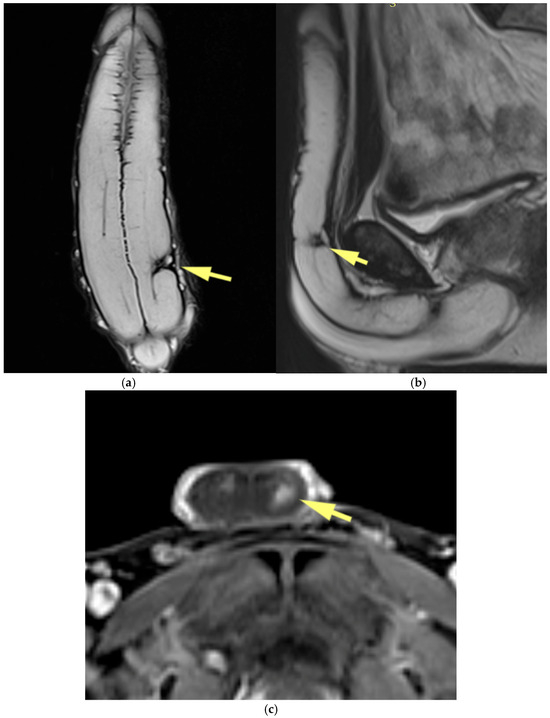

MRI of the Scrotum and Penis: Current Applications and Clinical Relevance

Background: Magnetic resonance imaging (MRI) plays an increasingly important role in the evaluation of scrotal and penile disorders, complementing ultrasonography in cases where findings are equivocal or complex. With its superior soft-tissue contrast, multiplanar capability, and advanced functional sequences, MRI provides unparalleled anatomic and tissue characterization across a wide range of male genital pathologies. Summary: This review summarizes current clinical applications of MRI in scrotal and penile imaging and discusses its diagnostic value, protocol optimization, and interpretive features. In scrotal pathology, MRI accurately differentiates torsion, trauma, infection, and neoplasms, aiding in the distinction between benign and malignant testicular lesions and supporting testis-sparing management. Quantitative diffusion and perfusion metrics further refine lesion characterization. In andrology, MRI biomarkers such as apparent diffusion coefficient (ADC), magnetization transfer ratio (MTR), and proton spectroscopy serve as promising non-invasive indicators of spermatogenic activity in male infertility. In penile imaging, MRI enables precise local staging of carcinoma, assessment of plaque morphology and activity in Peyronie’s disease, evaluation of tissue viability in priapism, and detection of prosthesis-related complications. Conclusions: MRI has become an essential problem-solving tool in the assessment of scrotal and penile diseases, enhancing diagnostic confidence and surgical planning. Future directions include protocol standardization, quantitative parameter validation, and the integration of radiomics and artificial intelligence to improve reproducibility and clinical impact. Full article

Figure 1